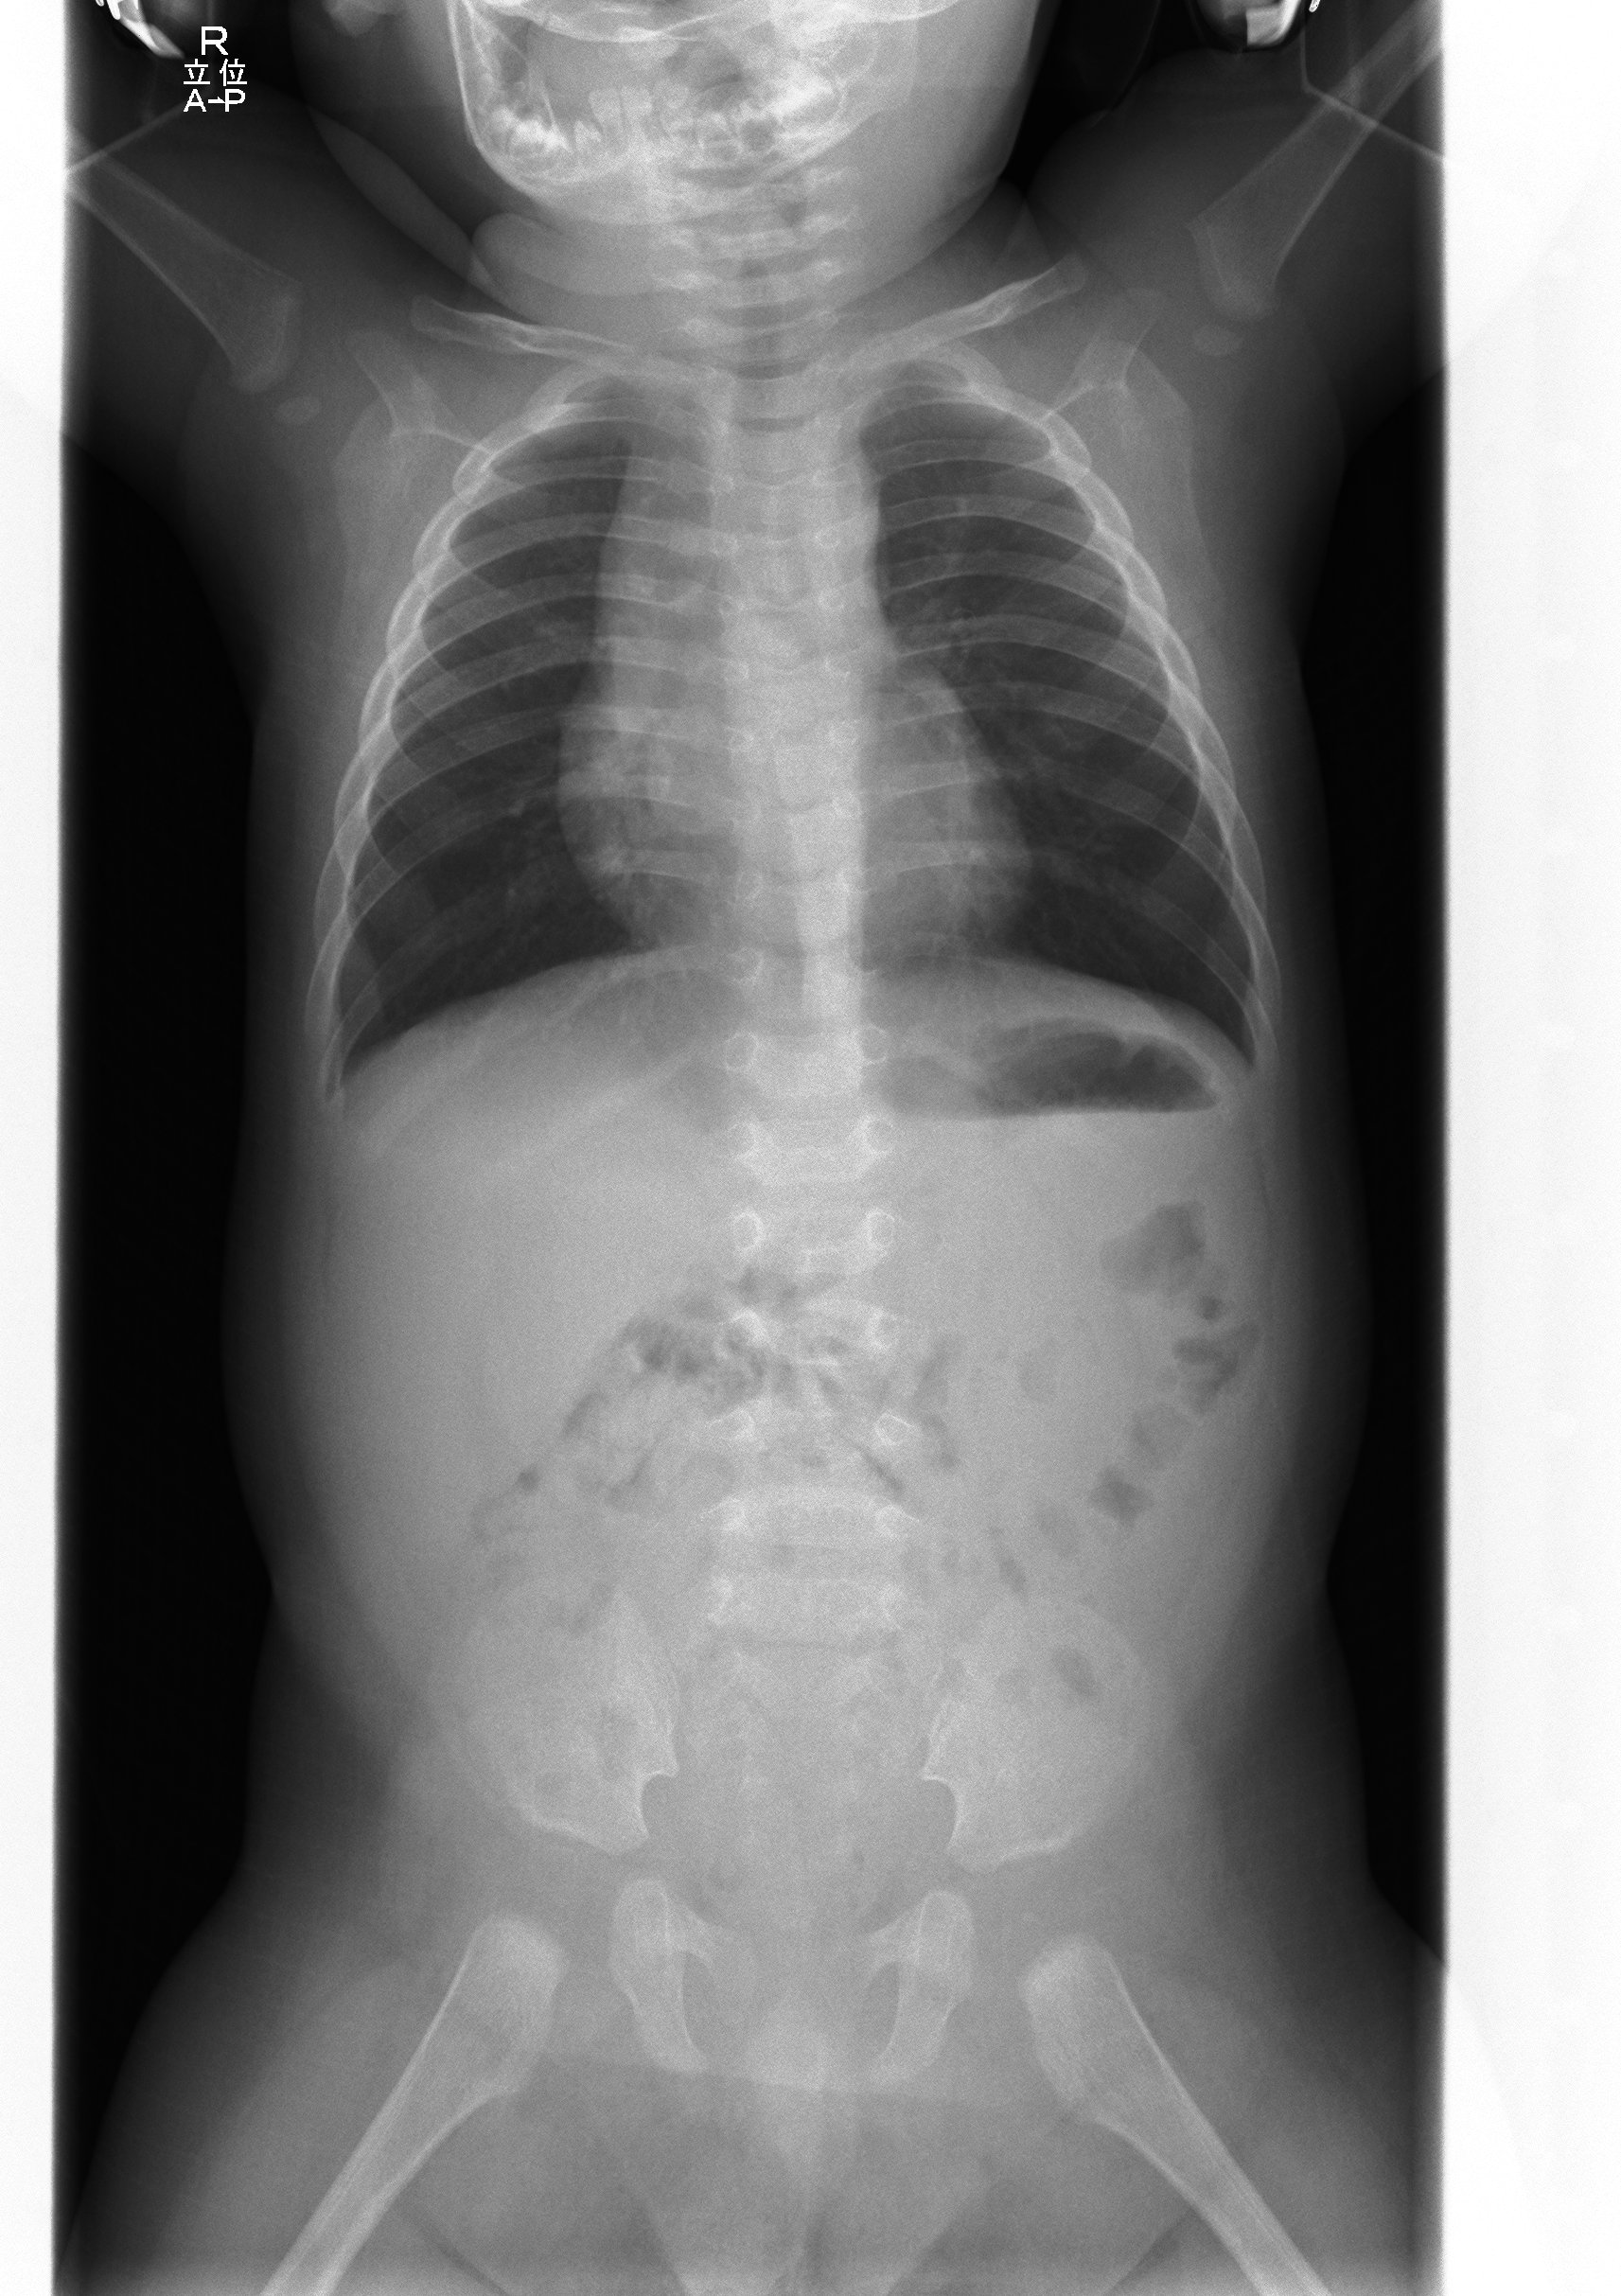

胸部、腹部や骨のX線写真を撮影する検査です。

胸部撮影は息を吸って、肺に空気がたくさんはいった状態の時に撮影を行います。新生児・乳幼児等の息を吸って息止めがうまくできない患者さんの場合は、胸やお腹の動きを見ながらタイミングを見て撮影します。骨の撮影は全身を対象としています。立位や坐位、臥位など、いろいろな体位で撮影します。

正確な体位の写真を撮るために、撮影部位をしっかり固定します。この時に、お子さんが大きな声で泣く事がありますが、私たちにとって、泣き声は最も大切なバイタルサインの一つです。

DRとはDigital Radiographyの略で、デジタル化されたX線写真のことです。このDRを応用し、体の広い範囲を一度に撮影できるようにしたのが長尺DR撮影です。当院では主に頸椎から腰椎までの全脊椎、骨盤から足底までの全下肢での撮影に使用しています。長尺DR撮影は、撮影時に静止が難しい小さなお子さんや、長時間立てないような方にでも、短時間で撮影が可能となり、患者さんの負担を軽減できるのが特徴です。この装置は各部屋1台ずつ計2台設置されており、日々稼働しています。

胸腹部立位撮影